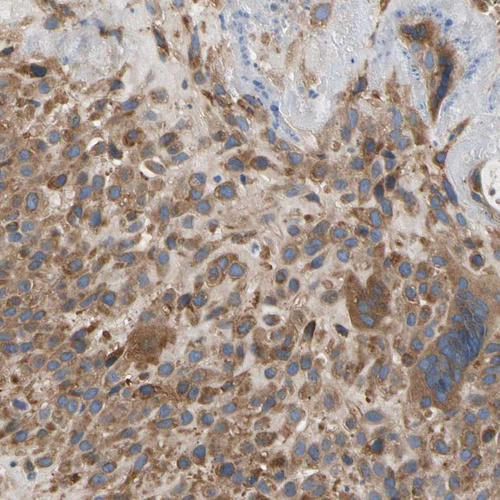

Immunohistochemical staining of human placenta shows weak to moderate cytoplasmic positivity in trophoblastic cells.